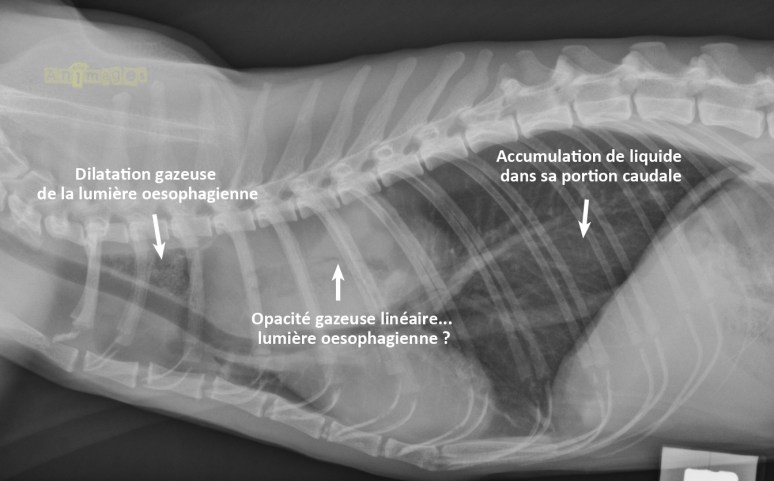

Il existait plusieurs différentiels pour cette large masse dont la position anatomique et le déplacement de la trachée et de la silhouette cardiaque laissaient présager une localisation médiastinale dorsale. L’opacité gazeuse triangulaire crânialement à la masse correspond à de l’air dans la lumière oesophagienne, alors que l’oesophage caudal semble légèrement dilaté par du liquide, ou épaissi. Une tomodensitométrie aurait été une excellente modalité pour confirmer sa localisation et compléter son bilan d’extension, qu’une chirurgie soit envisageable ou non. L’échographie a cependant été proposée car elle peut être réalisée sans anesthésie générale et permet de guider des cytoponctions, tout ça à moindre coût que la tomodensitométrie (CT scan). Voici ce qui a été trouvé…